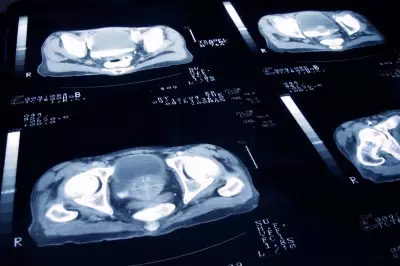

Health